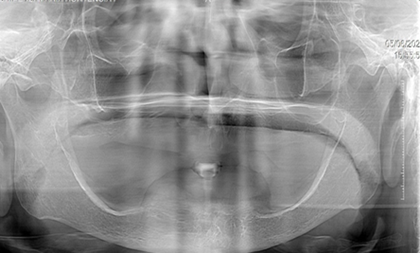

Fotografía del maxilar inferior (Figura 1).

Figura 1. Maxilar Inferior.

Elaboración: Los autores.

La paciente lleva usando una prótesis 10 años, debido a la irregularidad de rebordes que presenta la mandíbula, se considera desde el punto protésico un caso deficiente.

Paciente presenta elevaciones irregulares en el maxilar inferior (Figura 2).

Figura 2. Radiografía del maxilar inferior.